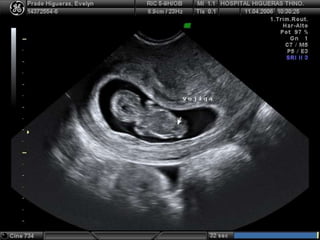

Hernia umbilical fisiológica (11sem) Inserción normal del cordón (12 sem)